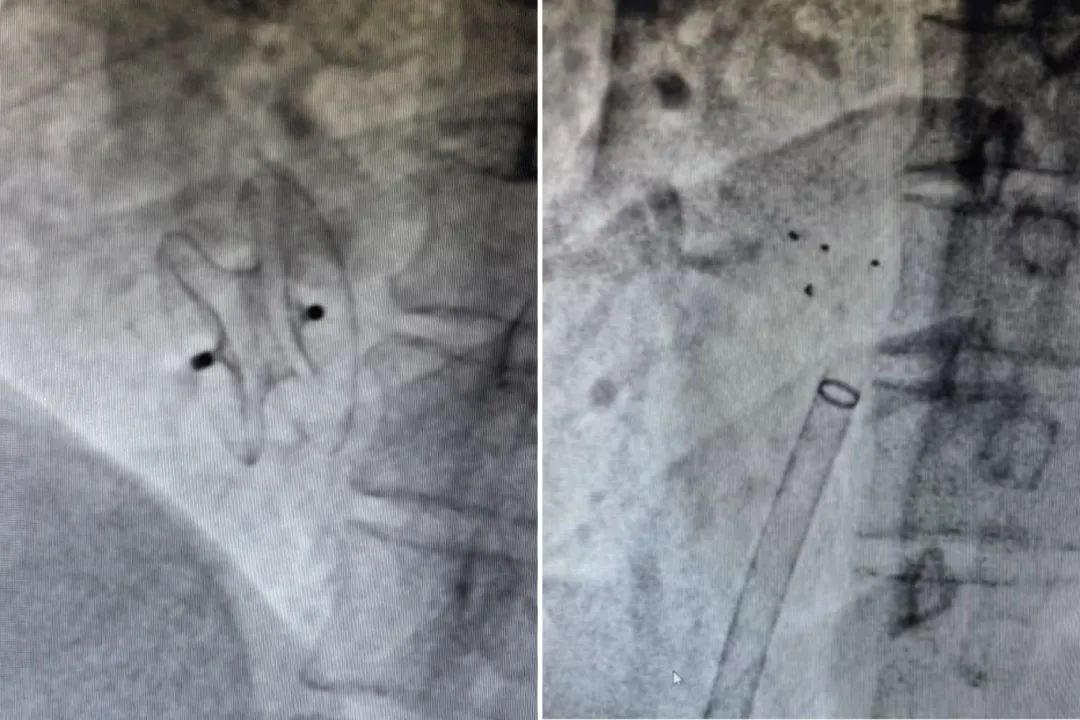

传统金属封堵器(图左);全可降解封堵器(图右)